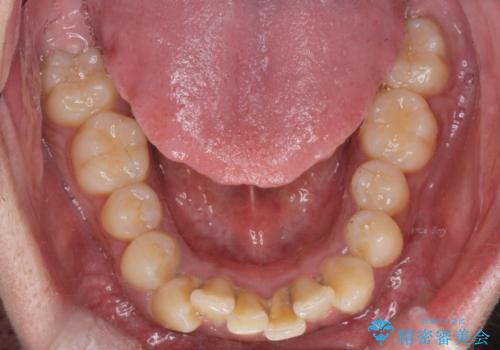

- 奥歯の噛み合わせは特に問題ないため臼歯を特に大きく動かす事はなく。

歯と歯の間を削る(ディスキング)、拡大を行いマウスピースで矯正を行いました。

がたつきもなくなりスッキリした歯並びになりました。

がたつきが無くなると歯ブラシがしやすくなり汚れが溜まりにくい口腔環境ができます。